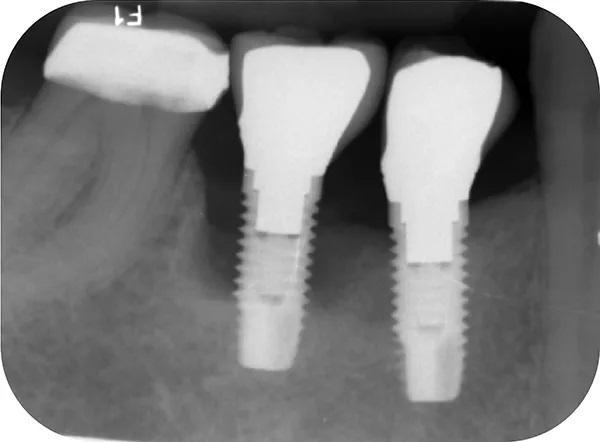

Пациент отрицал наличие вредных привычек к курению табака, а так же наркотических веществ таких как марихуана, либо пристрастия к другим видам наркотиков. Он не смог вспомнить, когда именно ему были удалены все первые премоляры и зубы мудрости по ортодонтическим показаниям, но отметил, что это произошло до имплантации. 2006 году ему были установлены имплантаты № 3, установленных в боковых отделах нижней челюсти для замещения зубов 4.4. и 4.5.. В 2012 году у него был диагностирован периимплантит в области данных имплантатов, однако в то время он не обращался за рекомендованным лечением. Рентгенографическое исследование периапикальной рентгенограммы, сделанной в 2012 году, показало 50% или более потери костной массы вокруг имплантата зуба 4.5., и около 15 % утраты костной ткани вокруг имплантата зуба 4.4 (фото 1). В декабре 2014 года имплантат зуба 4.5. выпал во время обычного акта жевания, из-за чего пациент не стал продолжать лечение. На фото 2 показан образовавшийся дефект альвеолярного отростка через 2 года после отторжения имплантата зуба 4.5.

Фото 1. Демонстрирует прицельный снимок зубов пациента со значительной убылью костной ткани вокруг имплантатов 4.4 и 4.5.